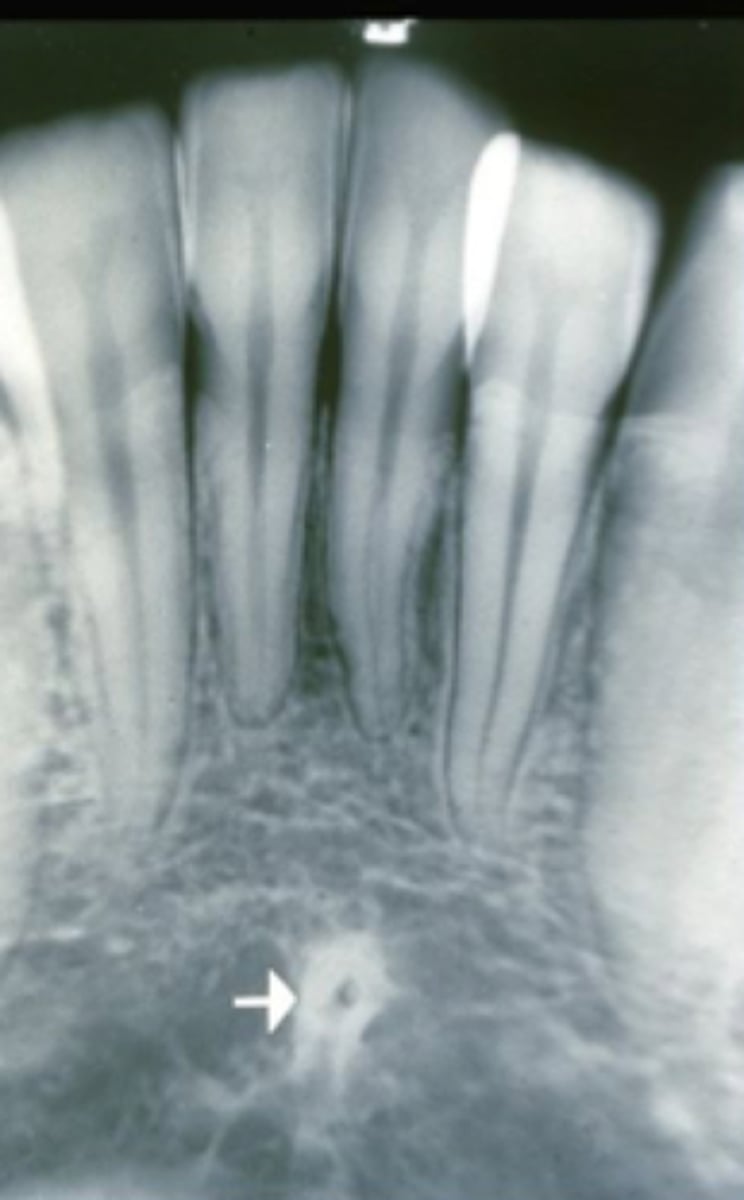

median suture

"crack" between roots of maxillary central incisors

area of incomplete fusion

radiolucent

incisive foramen

hole in the bone of the maxilla and between roots of incisors